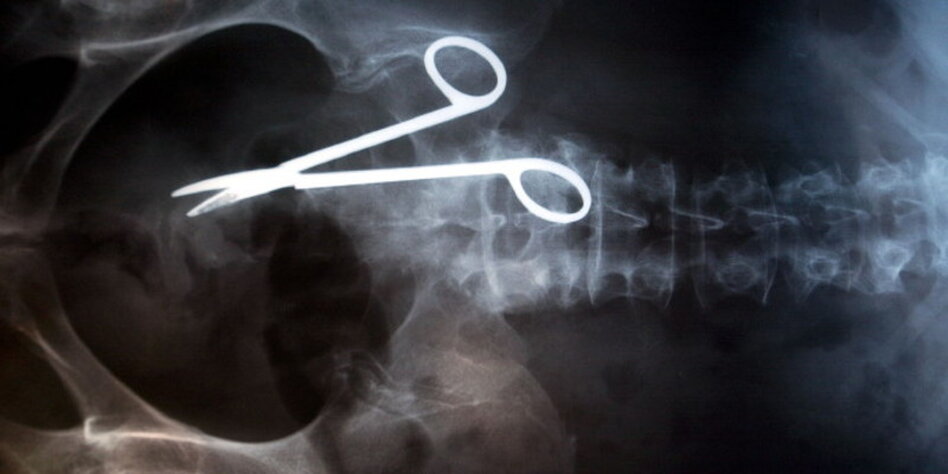

(IMG) Bild: Vergessene Arztschere im Körper einer Australierin, 18 Monate nach der OP per Röntgenbild diagnostiziert.

Insgesamt beschweren sich laut Bundesärztekammer im Jahr rund 40.000

Menschen über angeblichen Ärztepfusch, davon landet allerdings nur ein

Viertel bei den außergerichtlichen Schiedsstellen. Der Rest werde direkt

über die Haftpflichtversicherer und Krankenkassen aufgearbeitet - oder

landet gleich vor Gericht. Darunter seien vor allem schwere Fälle, etwa

wenn bei einer Operation fälschlicherweise das linke anstelle des rechten

Beins amputiert oder das Operationsbesteck in der Bauchhöhle vergessen

wurde.